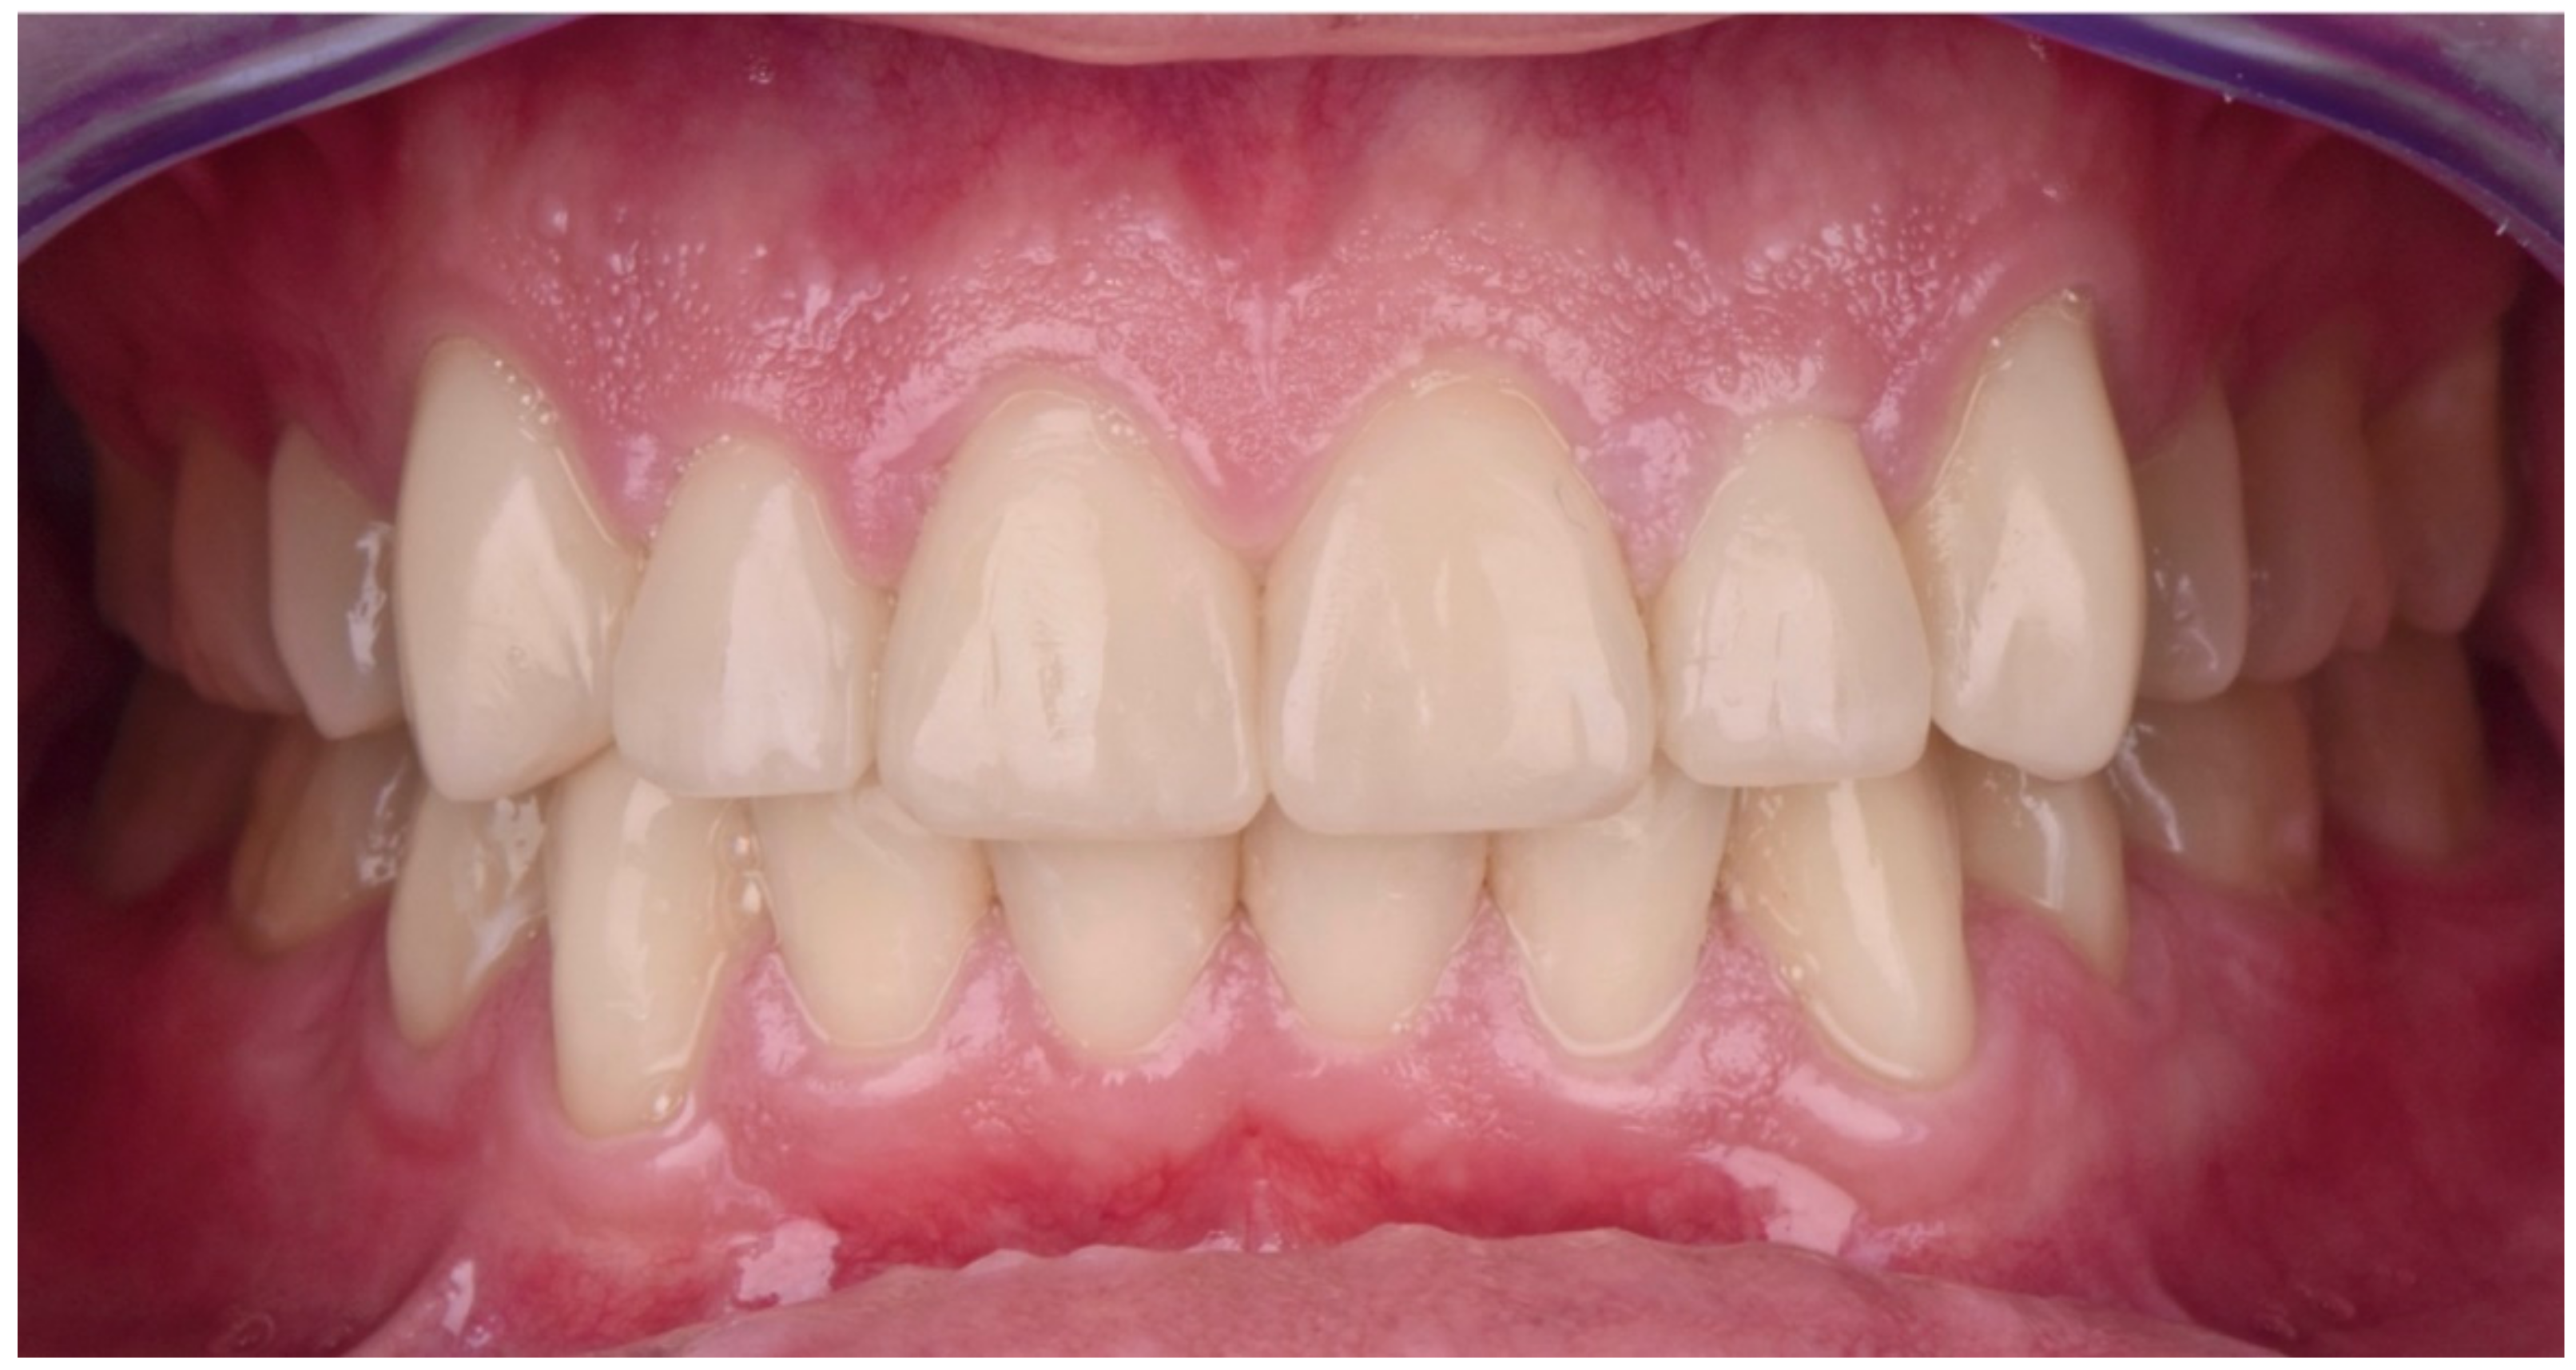

2.2. Restorative Phase